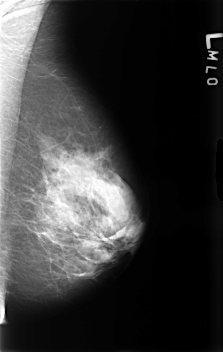

B_3464_1.LEFT_MLO

LEFT_MLO LINES 4568 PIXELS_PER_LINE 2896 BITS_PER_PIXEL 12 RESOLUTION 50 NON_OVERLAY